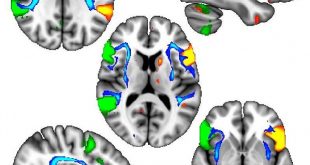

نوروسافاری| تحقیقات جدید محققان دانشگاه آرهوس نشان داده که ممکن است سرمنشا آغاز بیماری پارکینسون، یک باکتری دستگاه گوارش باشد که از طریق عصب‌ واگ به مغز منتقل می‌شود.

به گزارش نوروسافاری به نقل از ایسنا، محققان در این بررسی، عصب واگ معده ۱۵ هزار نفر را مورد مطالعه قرار دادند. این عصب در برخی از این بیماران قطع شده بود.

اگر شروع پارکینسون از درون روده باشد، پس بیمارانی که عصب واگ آنها قطع شده، باید از ابتلا به این بیماری محافظت شده باشند.

این پژوهش شواهد محکمی از آغاز پارکینسون در روده و انتقال آن به مغز از طریق عصب واگ را ارائه کرده است. همچنین محققان دریافتند بسیاری از این بیماران پیش از تشخیص پارکینسون از ناراحتی‌های روده رنج می‌بردند.

فرضیات پیشین درباره ارتباط بین پارکینسون و عصب واگ در مطالعات حیوانی مطرح شده بود. اگرچه تحقیق حاضر اولین و بزرگترین مطالعه‌ایست که این فرضیه را روی انسان‌ها مورد آزمایش قرار داده است.

به گفته محققان، با شناسایی ارتباط بین عصب واگ و گسترش بیماری پارکینسون باید تحقیقات در زمینه بررسی عوامل ایجاد این مشکل عصبی ادامه یابد. در این صورت می‌توان از گسترش این بیماری جلوگیری کرد که دستیابی به آن موفقیت بزرگی در علم پزشکی محسوب می‌شود.